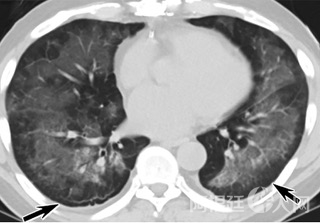

疑点一,电子烟患者的CT影像和临床表现并不具有特异性。所谓美国电子肺炎患者,其实是对没有其他合理诊断证据、吸食电子烟肺炎患者的统称。这些患者在病发前90天内吸食了电子烟,尤其值得注意的是,部分患者的CT影像特征和临床表现与病毒性肺炎患者极其相似。

中、下肺轴位CT平扫显示毛玻璃样混浊伴胸膜下保留(箭头)。(同一病人CT影像)